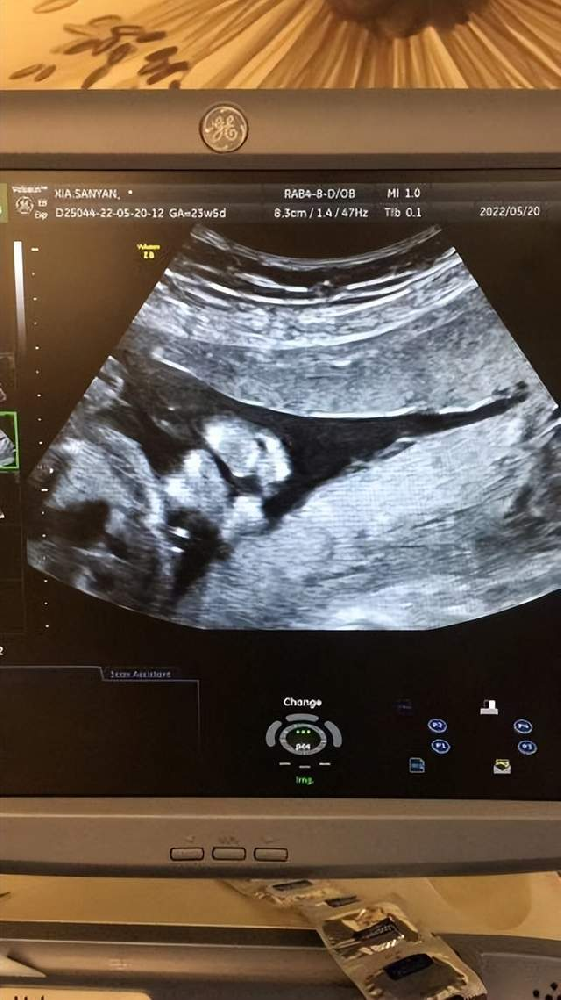

新生命的誕生對于一個家庭來說是再幸福不過的一件事。隨著生育政策的放開,越來越多的家庭選擇生育二胎。但在迎接新生命的同時,許多“二胎”孕婦認(rèn)為自己已經(jīng)是“熟手”,···